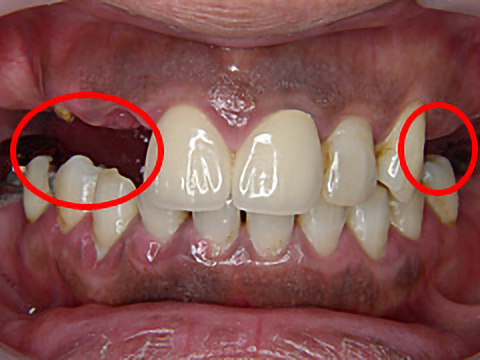

症例3

年齢 | 42歳 |

---|---|

性別 | 女性 |

費用 | 1本あたり330,000円+保険で必要な金額(抜歯など) |

治療期間/治療回数 | 1年半/20回 |

治療におけるリスク |

骨の状態により治療ができない場合があります。 一度埋め込んだインプラントが脱離する可能性があります。 上部構造は消耗品です。一生持つものではなく、破折する可能性があります。 |

歯科治療が怖くて長きにわたりお口を放置されていましたが、一大決心の後、当院にて治療を受けられました。

右上4本、左上も3本、抜歯即時埋入を含めてインプラント治療を受け、噛み合わせを取り戻すことができました。また、下顎の前歯も大きくすり減っていたため、オールセラミックスで治療しました。